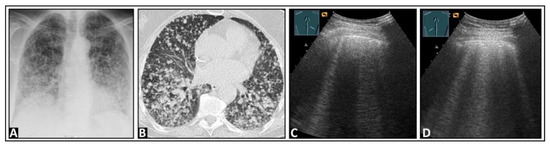

5. Pneumonia

6. Interstitial Lung Disease

7. Other Pathologic Situations